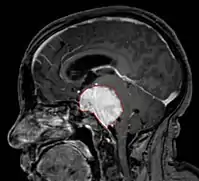

Imaging

- Benign Meningioma on MRI

- MRI

- Preferred imaging because it can show dural origin

- Dural tail sign seen in about two-thirds: characteristic marginal thickening that tapers peripherally along the dura

- Isointense on T1, hyperintense (usually homogeneously) on T2, strong enhancement with IV contrast